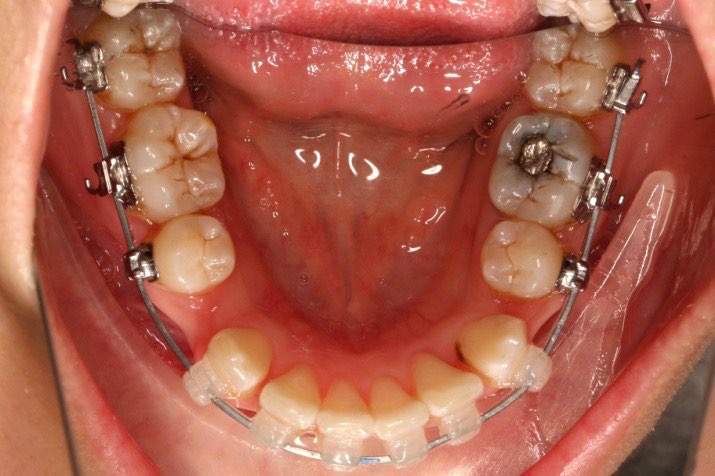

5.第7个月:2017.05.26 ◆ 下颌36/46加power arm

2017.05.26  磨牙近中倾斜,下颌36、46加power arm

下颌磨牙通过powerarm直立效果明显,下颌整平效果明显

2017.05.26